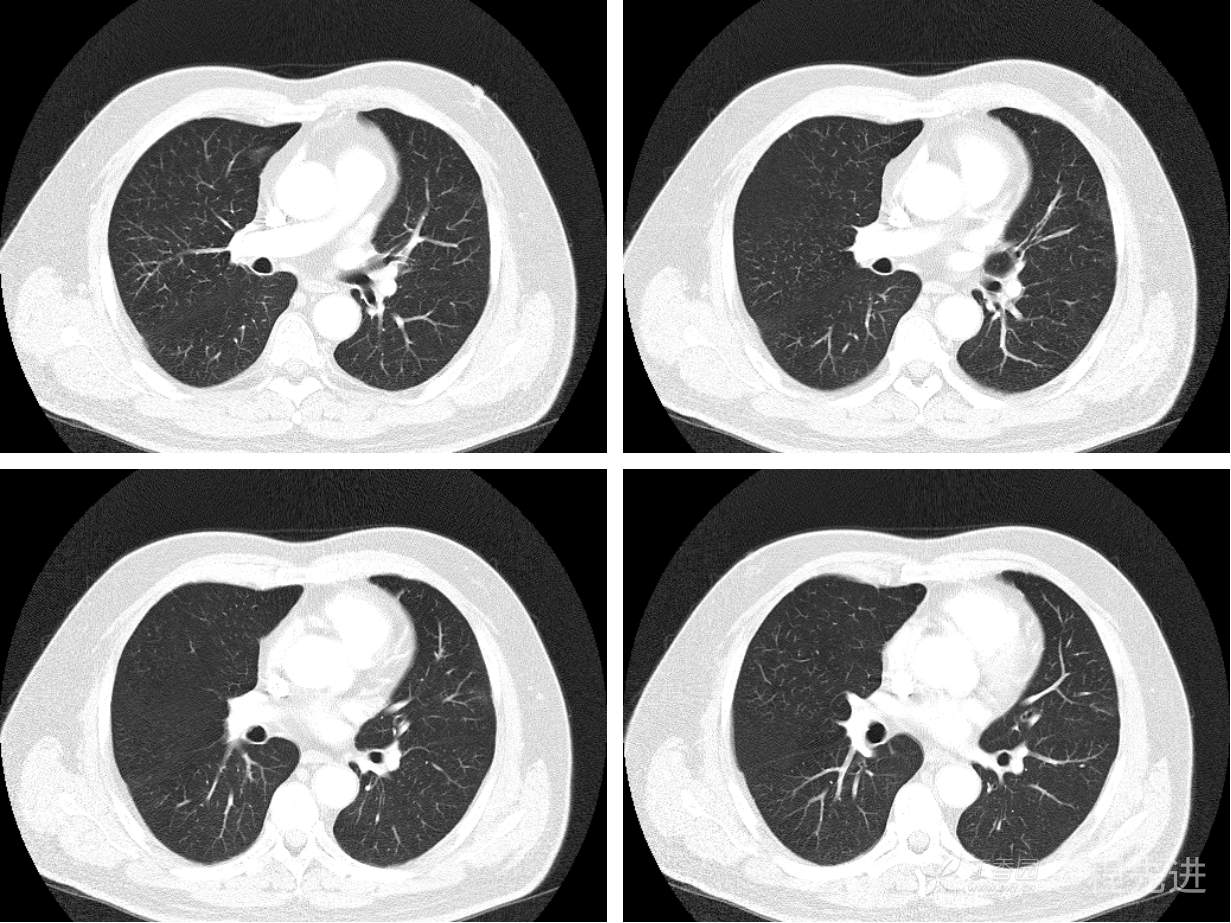

现病史概要:患者入院前约半月无明显诱因下出现咳嗽、胸闷症状,无明显发热症状,咳少量白痰,无明显咯血、喘息、头晕等不适,就诊我院查胸部CT示上纵膈肿物,左肺上叶支气管内肿物,现为行进一步治疗收入胸外科,患者近来饮食睡眠尚可,二便如常。